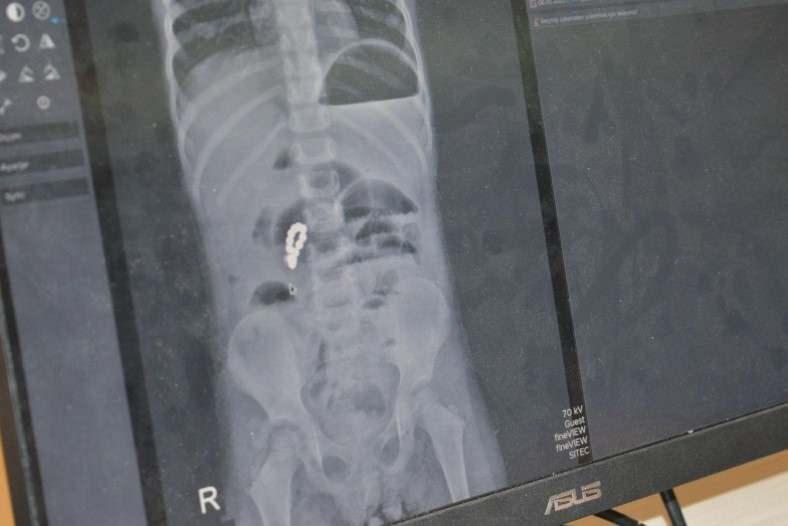

Peker’in mıknatıs yuttuğundan habersiz olan ailesi, karın ağrısı, bulantı ve kusma şikayetleri üzerine kızlarını Nusaybin Devlet Hastanesi’ne götürdü. Yapılan röntgende yabancı cisim tespit edilmesi üzerine Peker, Mardin Eğitim ve Araştırma Hastanesi’ne sevk edildi.

Peker’in bağırsaklarında farklı zamanlarda yuttuğu 8 adet boncuk mıknatısın birbirine yapışarak bağırsakları deldiği ve tıkadığı belirlendi. Yaklaşık 3 saat süren ameliyatta bağırsaklar tek tek onarıldı. Ağır geçen operasyonun ardından 6 gün yoğun bakımda kalan Peker, sağlığına kavuşarak taburcu edildi.

Ufak parçacıklı oyuncakların özellikle 6 yaşından küçük çocuklara verilmemesi gerektiği konusunda aileleri uyaran Op. Dr. Mürsel Haspulat, “Basit görünen bir oyuncak çocuğumuzu ölümle burun buruna getirdi. Bu tür mıknatıslar bağırsaklarda birleşerek hayati risk oluşturabiliyor. Aileler özellikle kış aylarında çocuklarını küçük ve parçalı oyuncaklardan, pillerden ve sert gıdalardan uzak tutmalı. 4 yaşındaki Eda, karın ağrısı ve kusma şikayetiyle geldi. Normalde basit bir şekilde apandisit ya da bağırsak düğümlenmesi diye düşünebildiğimiz bir vakaydı. Ama sonrasında röntgenlerini çekip hızlıca ameliyata almamız gereken bir durumla karşı karşıya kaldık. Çünkü ailenin de fark etmediği şekilde 2-3 hafta içinde tane tane mıknatıs parçalarını yutmuş ve bu mıknatıs parçaları bağırsakları birbirine yaklaştırarak düğümlenmesine ve delinmesine neden olup çocuğun bağırsaklarının tıkanmasına neden olmuştu. Ameliyatta öncelikli karmaşık tabloyu tek tek çözerek delinmiş bağırsak kısımlarını onardık. 3 saat boyunca uğraştık, devamında ameliyatın ortasında röntgen çektik tekrar içeride başka bir parçacık var mı diye kontrol ettik. Bir tane kalmıştı, onu da çıkartıp ameliyatı tamamladık. Fakat çok ağır bir ameliyat olduğu ve genel durumu da bozulmuş olduğu için çocuğumuz 6 gün boyunca yoğun bakımda yatmak zorunda kaldı. Yoğun bakımda 3’üncü gününde çok şükür beslenmeye başladı, daha sonra da servisi aldık. Şu anda taburcu ettik. Çok iyi ve şanslı bir vaka olarak sonuçlandı. dedi.